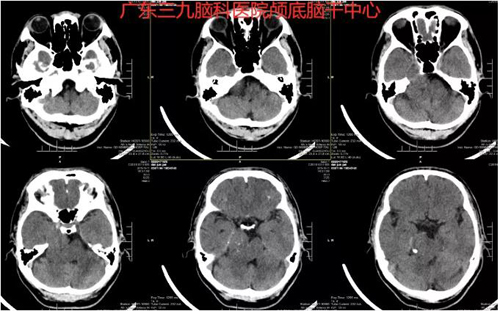

图1:术前CT示右侧桥小脑角区-岩斜部示团片状稍高密度影,其内散在斑点状致密影,范围约37×25×33mm,脑干右侧受压,余脑实质形态、大小、密度未见异常。